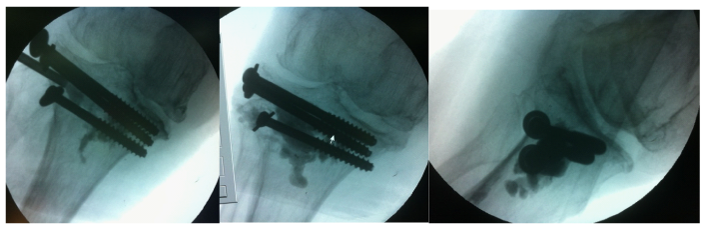

The optimal position for balloon placement was predetermined using the CT scanning. In the operating room the patient was placed in supine position on the operating table and a fluoroscopic unit was readily available. Under spinal anesthesia, a clinical stability test was applied, which did not reveal any ligamentous injury. After skin preparation and draping, a trocar was introduced in the lateral tibial plateau through a stub incision and advanced to the predetermined position - below the depressed fragment - using fluoroscopic control. Three Kirschner wires were placed just below the trocar, to act as a palisade, supporting the subsequent balloon inflation (Figure 2). We started slowly inflating the balloon with contrast solution to an initial pressure of 50 psi, without any radiographic evidence of balloon asymmetry, indicative of malpositioning. We then fully inflated the balloon to approximately 250psi, effectively raising the depressed tibial plateau (Figure 3).

Figure 2 Operative room and draping, trocar and supporting K-wires introduction.